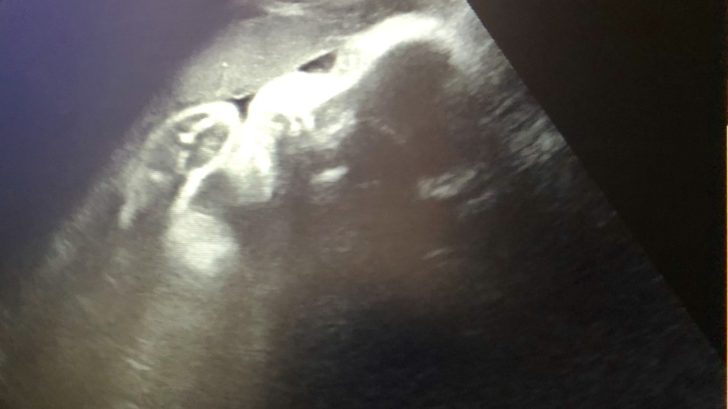

Další velký ultrazvuk

Těšila jsem se, že mrňouse zase uvidím, budu vědět, že je vše v pořádku. Na další velký ultrazvuk se chodí kolem třicátého týdne. Já na něm byla až ve 32 tt. Vše je v pořádku, jen ještě není hlavou dolů, ale nemám se bát, to se do porodu může ještě několikrát změnit. A ačkoliv mám nahoře asi 12 kg, prcek má jen 1500 g. Je to prý v normě, ale já teda nevím, proč mám nahoře tolik? 😀 Pohlaví stále neznáme, pokud mě čtete pravidelně, víte, že se s manželem necháváme překvapit (chtěl to tak teda hlavně manžel, a já mu to slíbila). Tentokrát jsem se už ani nesnažila na ultrazvuku něco rozeznat, naopak, vlastně se na to překvapení strašně těším!